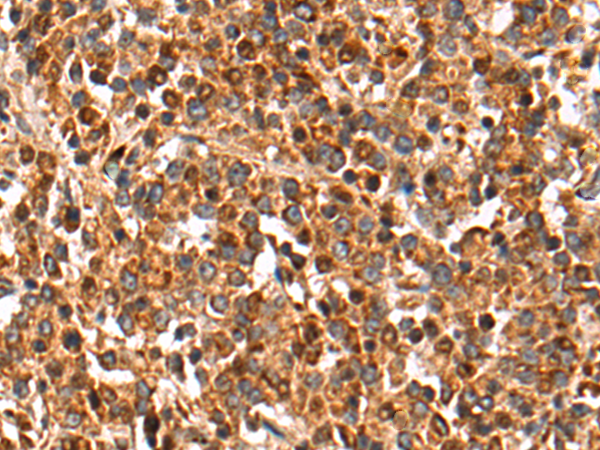

分类: 科研抗体货号: P10582别名: XB; TNX; XBS; EDS3; HXBL; TENX; TN-X; VUR8; TNXB1; TNXB2; TNXBS; EDSCLL; EDSCLL1应用: WB,IHC反应种属: Human, Mouse